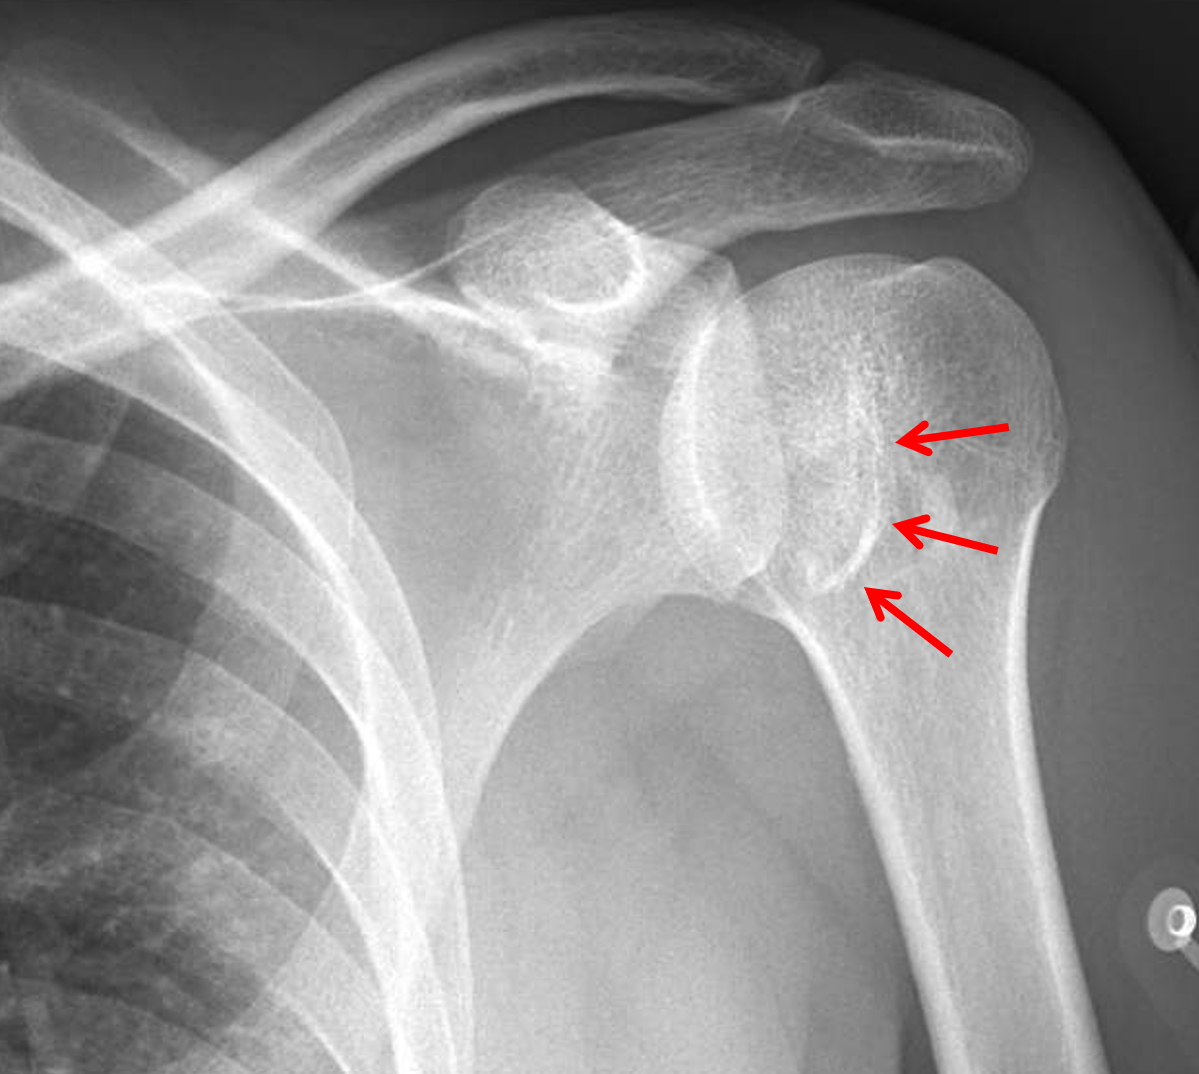

Shoulder dislocation with Bankart fracture Radiology at St. Vincent's Shoulder Fracture Vs Dislocation shoulder fractures most often involve the clavicle (collarbone), proximal humerus (top of the upper arm bone), or the scapula. shoulder dislocations are the most common of all major joint dislocations and frequently present to clinics and. The dislocation may anteriorly, posteriorly, inferiorly, or anterior. the shoulder is the most regularly dislocated joint in the body; Shoulder Fracture Vs Dislocation.